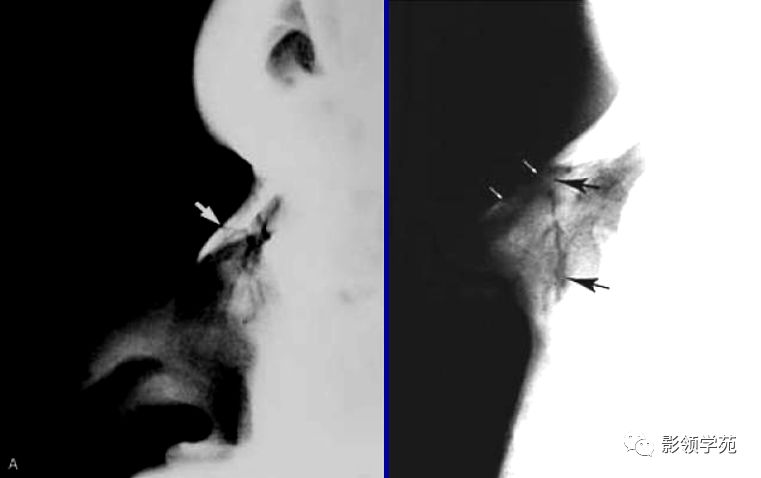

X线平片:侧位

鼻骨正常侧位